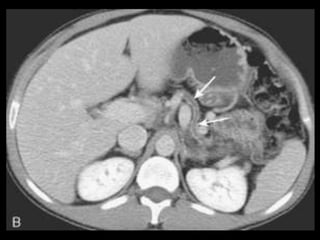

PANCREATITE AGUDA GRAVE

A administração de contraste IV é essencial,

especialmente em pacientes com PA grave, para

visualizar o pâncreas, diferenciar a glândula de

coleções líquidas adjacentes e do tecido

inflamatório peripancreático e demonstrar a

necrose pancreática.

Áreas focais ou difusas de realce diminuídas ou

ausente à TC contrastada dinâmica constituem

áreas de isquemia ou necrose.

TC tem precisão geral de 87% com S e E de 100%

para necrose extensa e 50% com áreas menores.